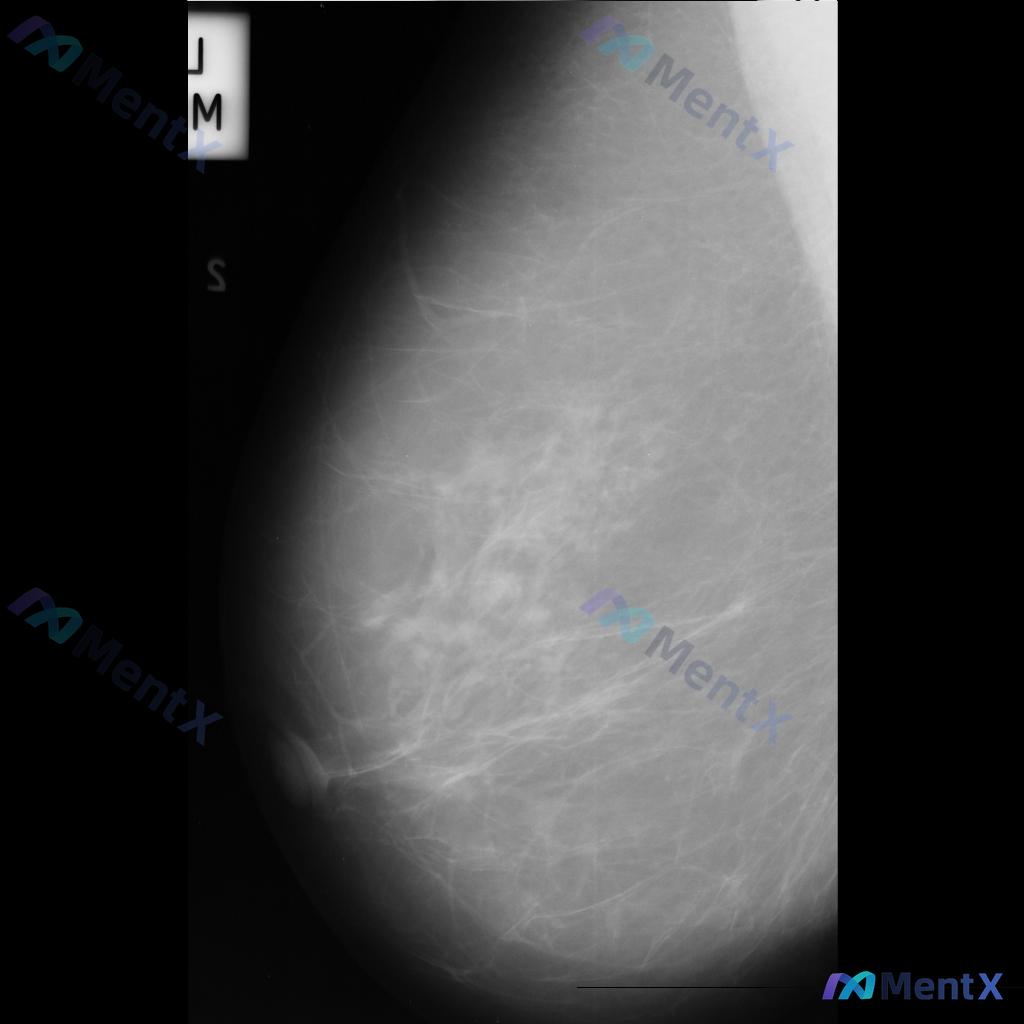

整理到一份单张乳腺钼靶影像的资料,分享给大家讨论: - 背景:乳腺整体为多量腺体型或致密型(BI-RADS C/D型可能) - 主要异常:在乳腺中下部略偏中央区域,可见局灶性不对称密度,或伴有轻度腺体结构紊乱 - 伴随征象:未见明确簇状/线样等可疑恶性钙化,无明确结构扭曲、皮肤增厚/回缩、乳头内陷等...

各位同道好,今天分享一则左乳钼靶病例,影像表现如下: 1. 左乳下方(近乳头区)可见一个边界清晰、形态卵圆形的等/稍高密度肿块影; 2. 左乳中央及下象限腺体局部密度增高和结构紊乱; 3. 散在分布的粗大点状钙化。 上传的钼靶影像编号为mdb083.png,供大家参考。 针对这组表现,你更倾向于哪种...